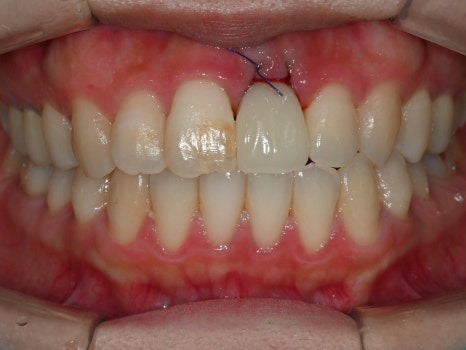

수술 당일 오후, 임시치아를 장착한 모습

수술 2-3시간 후 앞니 임플란트에

고정성 임시치아를 장착한 모습입니다.

수술 직후이기 때문에 봉합사(실)이 있지만,

임시치아임에도 주변 치아와 비교해서

이질감이 거의 없습니다.

틀니 형태가 아니기 때문에

식사 및 발음, 심미적인 기능에서

불편함은 거의 없다고 하셨습니다.

2개월 후, 마찬가지의 디지털 방식으로 스캔하고

제작한 최종 임플란트 치아를 장착할 수 있었습니다.

발치 및 즉시 임플란트 2개월 후

기존의 앞니가 약간의 변색이 있어서

오히려 마음에 들지 않았었는데

새로 제작한 앞니 임플란트 치아가 더 예뻐서

나머지 앞니를 바꾸고 싶다는 농담까지

하실 정도였습니다.